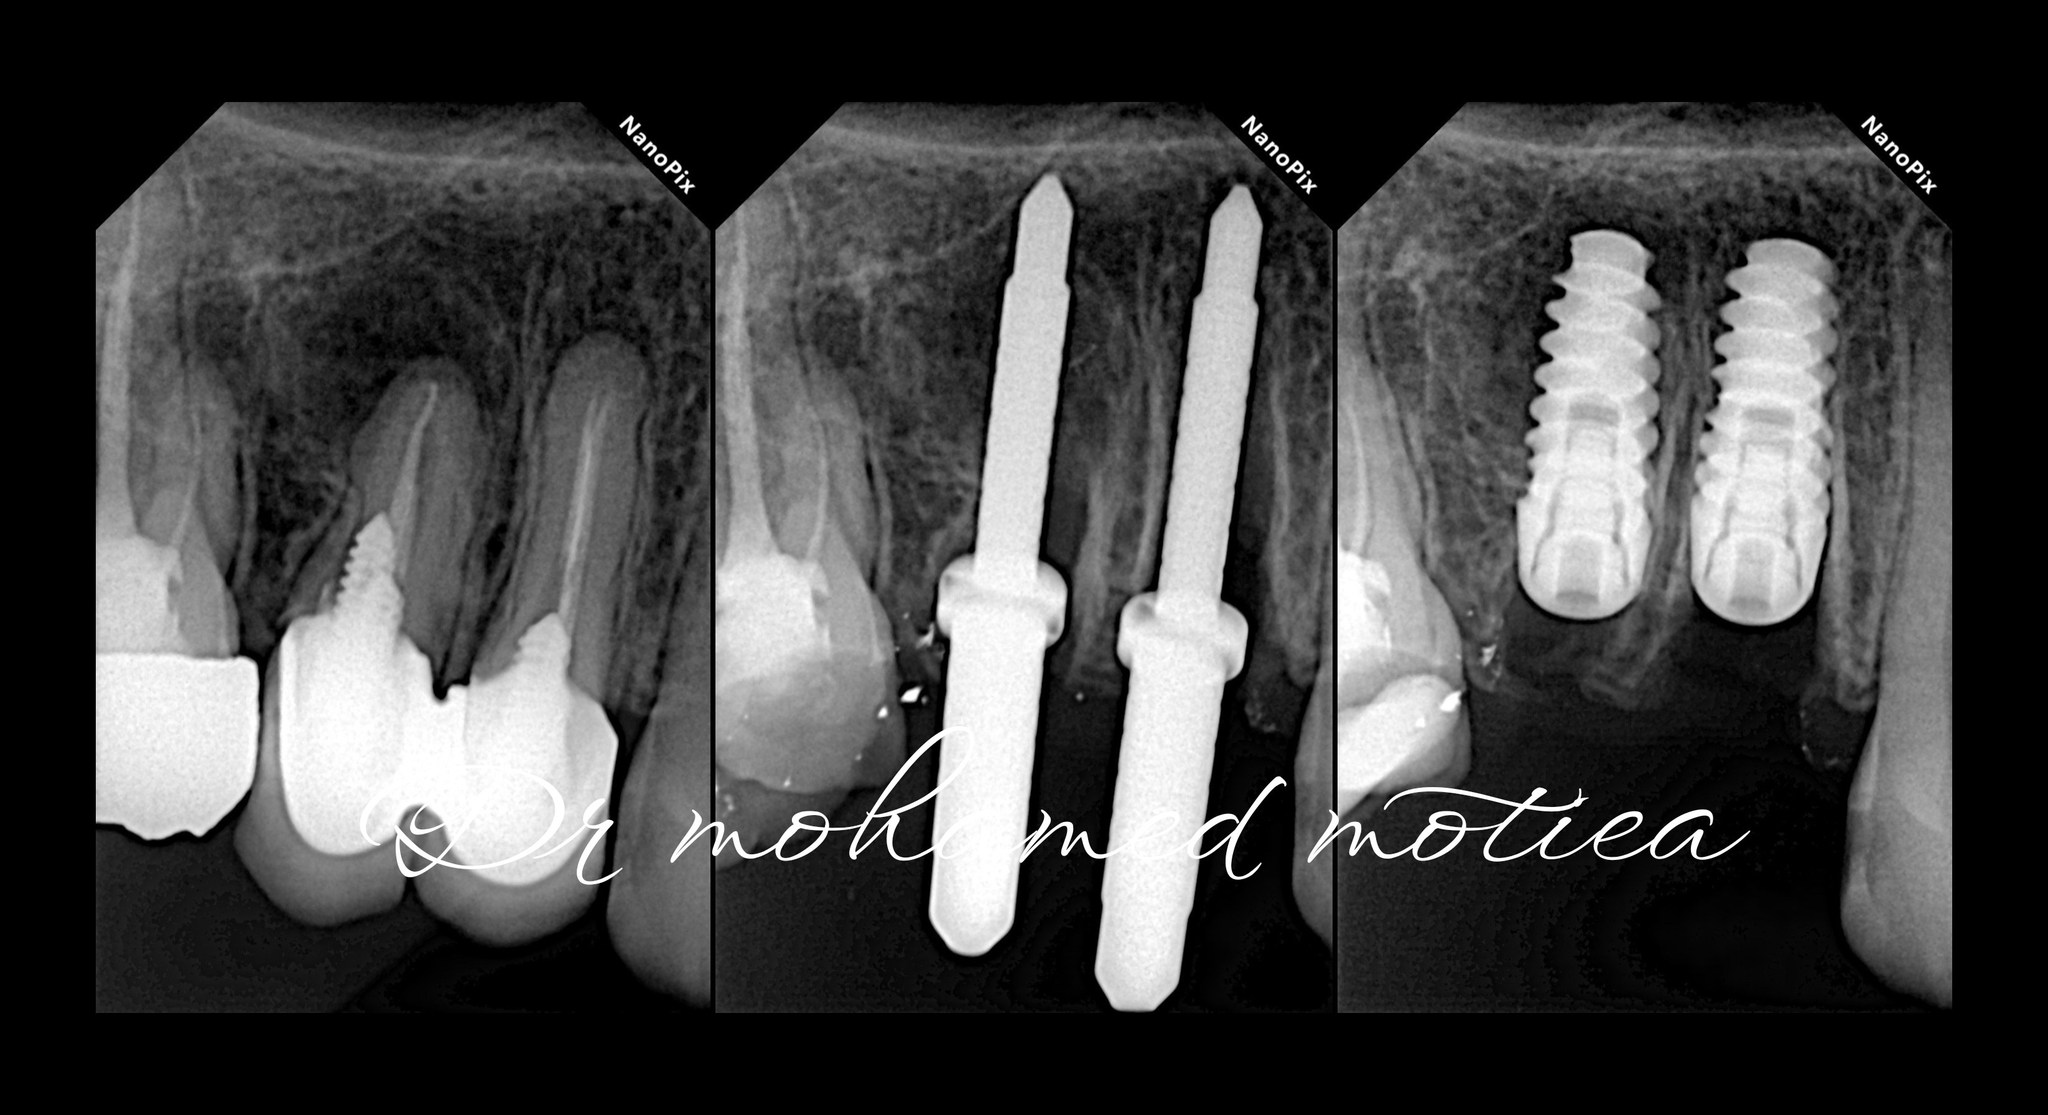

د. أدهم عاطف - زراعة TB Implant System للأسنان المفقودة

د. أدهم عاطف - زراعة TB Implant System في الفك السفلي الأيسر لتعويض فقد ضرس مع زراعة فورية.